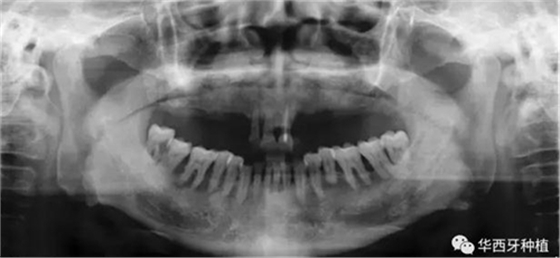

吳教授首先就全口牙缺失病種自身具有的特點(diǎn),進(jìn)行了總結(jié)。特別強(qiáng)調(diào)了嚴(yán)重的牙槽骨骨質(zhì)萎縮,其結(jié)合上下頜骨的解剖結(jié)構(gòu)(上頜竇,下齒槽神經(jīng)管)后導(dǎo)致的種植區(qū)骨量不足。

對于骨量較好的患者,選擇設(shè)計(jì)與手術(shù)方法較為簡單的傳統(tǒng)的組牙種植修復(fù),過程較為便捷,遠(yuǎn)期效果穩(wěn)定。但是時(shí)間與經(jīng)濟(jì)成本高,并且在全口牙缺失患者口內(nèi),由于參照物較少,種植體的位置,共同就位與平行度的選擇與構(gòu)建均存在一定難度。